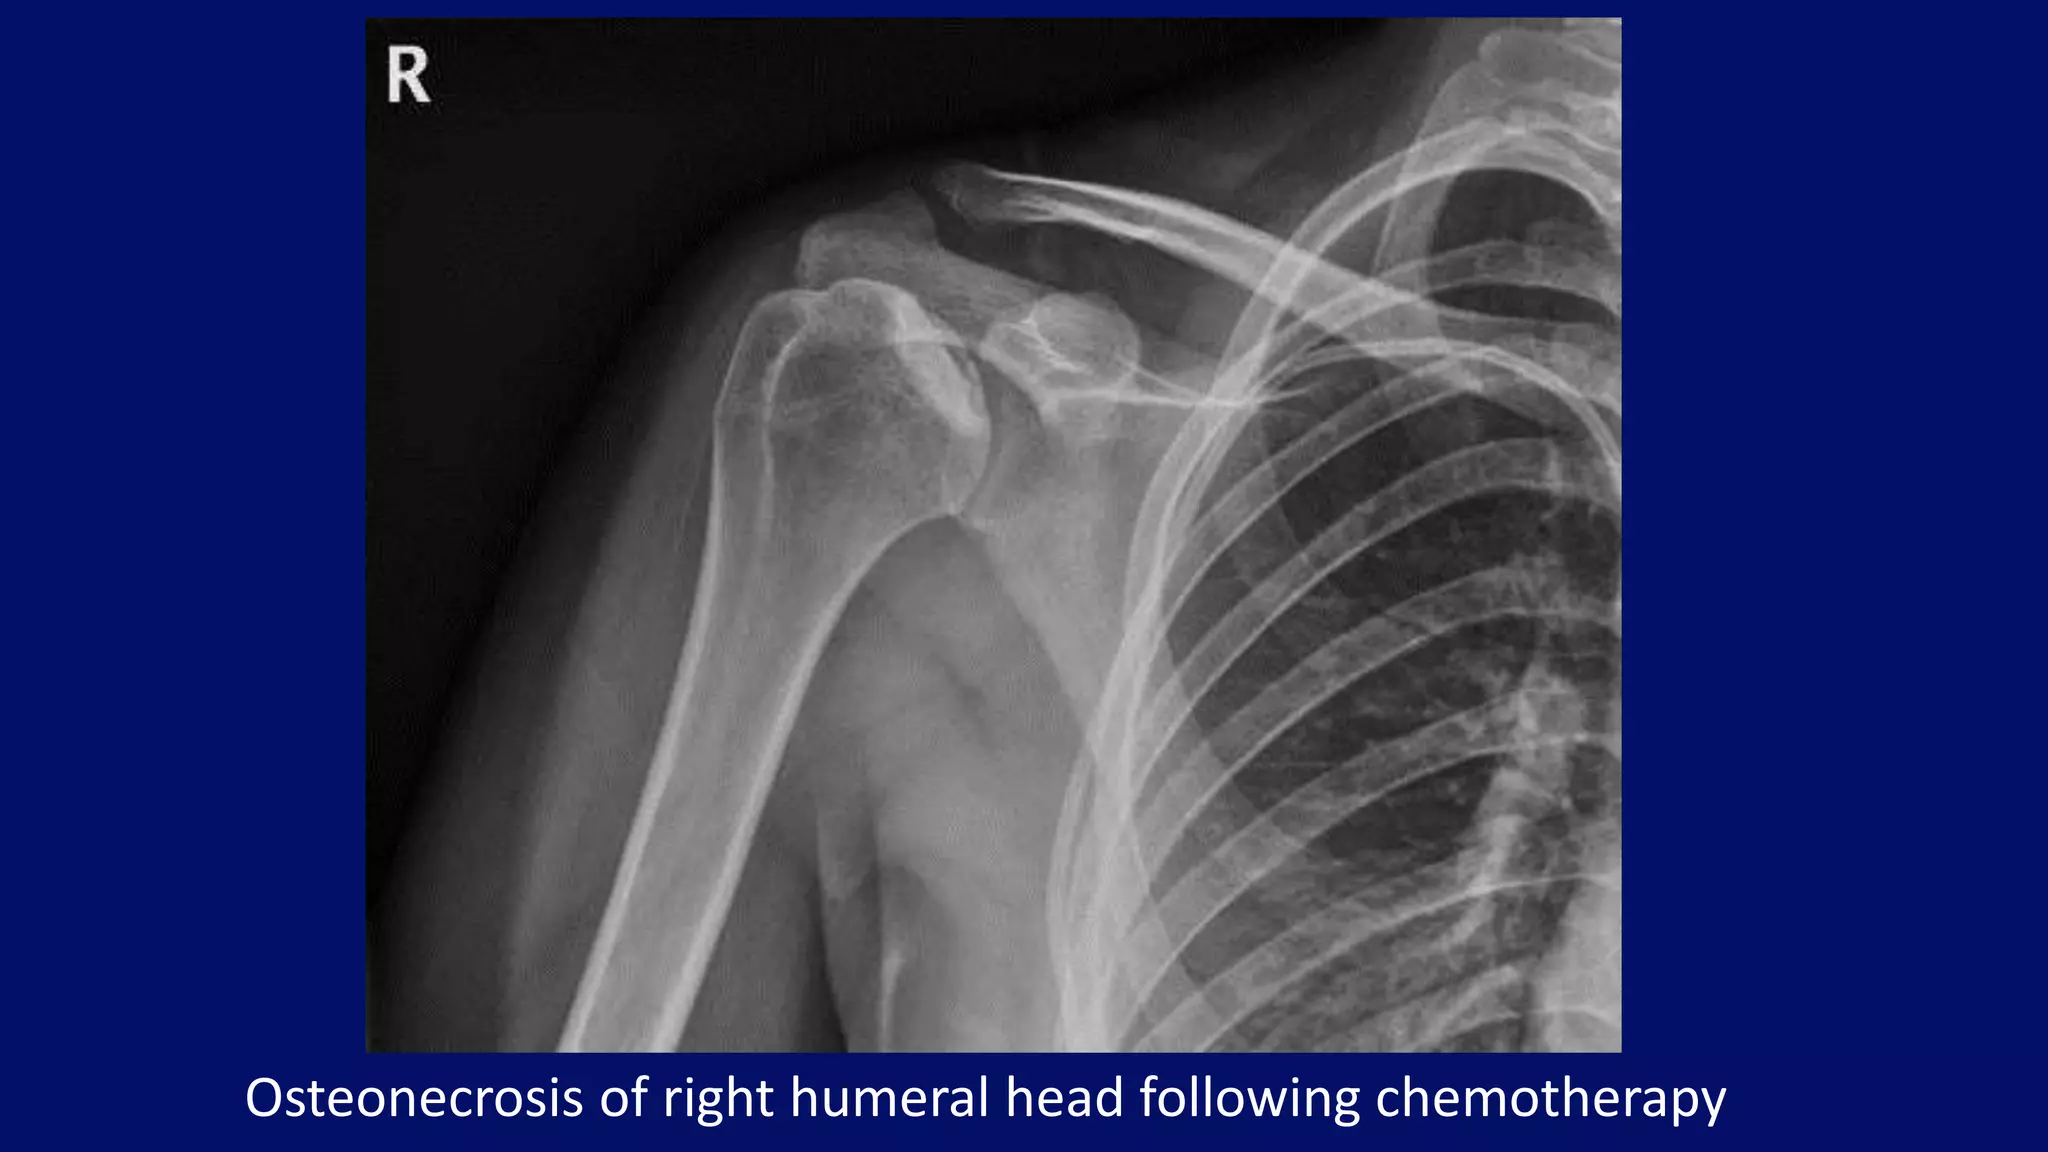

Osteonecrosis of right humeral head following chemotherapy